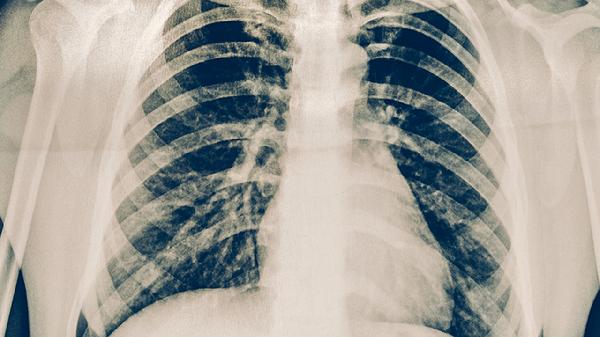

完成治疗后应每3-6个月进行胸部X线或CT检查,连续随访2年。出现咳嗽咳痰超过2周、低热盗汗、体重下降等可疑症状时需立即就诊。痰涂片和痰培养检查能早期发现细菌学复发。